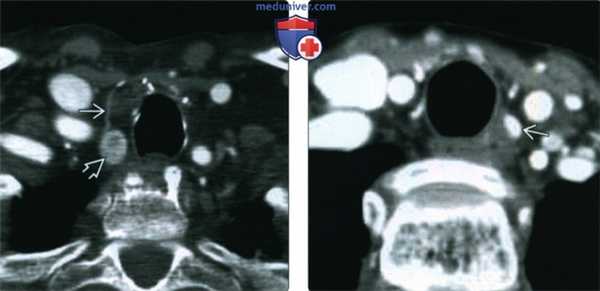

(Слева) КТ с КУ, аксиальная проекция. Новообразование с нечеткими контурами, расположенное в трахеопищеводной борозде, которое смещает щитовидную железу кпереди. Образование оказалось раком паращитовидной железы. Дифференциальный диагноз следует проводить с аденомой паращитовидной железы, а также экзофитной аденомой или раком щитовидной железы.

(Справа) УЗИ, аксиальная проекция на уровне перешейка щитовидной железы. Определяется гипоэхогенное однородное образование, расположенное позади правой доли щитовидной железы и смещающее щитовидную железу кпереди. Хотя образование имеет четкие контуры, оно оказалось паращитовидной карциномой. (Слева) Сцинтиграфия с технецием-99 сестамиби, прямая проекция, поздняя стадия. Нормальный захват радиофармпрепарата обеими поднижнечелюстными железами, а также патологический очаг в нижнем отделе шеи, представляющий собой рак паращитовидной железы. Аденома паращитовидной железы выглядела бы аналогично.

(Справа) КТ с КУ, аксиальная проекция. Крупное образование в щитовидной железе с нечеткими контурами, прорастающее в подподъязычные мышцы. И хотя обычно новообразования паращитовидных желез локализуются позади щитовидной железы, они могут располагаться и внутри нее. В таком случае их невозможно отличить от первичного рака.

• Чаще всего расположена за щитовидной железой, > 3 см

• Крупный размер и наличие плотной капсулы говорят в пользу злокачественности

• Крупная опухоль с признаками инвазивного роста; по сравнению с аденомой пациенты обычно более молодого возраста

• В диагностике используются технеций-99 сестамиби, сонография и КТ с контрастированием

• КТ с контрастированием/MPT: полезны для поиска эктопированных желез и оценки распространенности инвазивного процесса